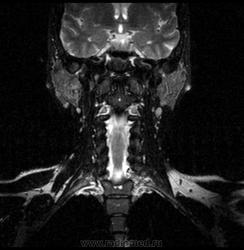

06.06.2011 МРТ - головы и шеи.

Пацентка 36 лет, с жалобами на припухлось в околоушной области справа.

В глубокой доле  правой околоушной железы  на фоне неизмененной паренхимы зона  гетерогенного по Т2, гипоинтенсивного по Т1  с единичными гиперинтенсивными включениями.При контрастировании- накопление контраста диффузное неоднородное и по периферии.Рискну предположить злокачественное образование ( аденокарцинома) с низкой степенью злокачественности( есть капсула, экспансивный рост).Сильно не расстреливайте.

Проблема в том, что перед челюстно-лицевым хирургом стоит распространенность любого объемного процесса, в данном случае все упирается в возмможную травму лицевого нерва и конечно же с дальнейшим его парезом, а ведь женщина  еще молодая. Образование имеет тонкостенную оболочку, по структуре неоднородно, с наличием кальцината, при этом МР-сигнал от окружающих анатомических структур(как костных так и мышечных) не изменен, т.е. об инфильтративном росте речи не идет, в какой то степени доброкачественное. В конкретном случае лицевой нерв с ретромандибулярной веной просто несколько оттеснен.

По гистологии аденома околоушной слюнной железы, но после удаления пока сохраняется парез лицевой мускулатуры, возможно временный.